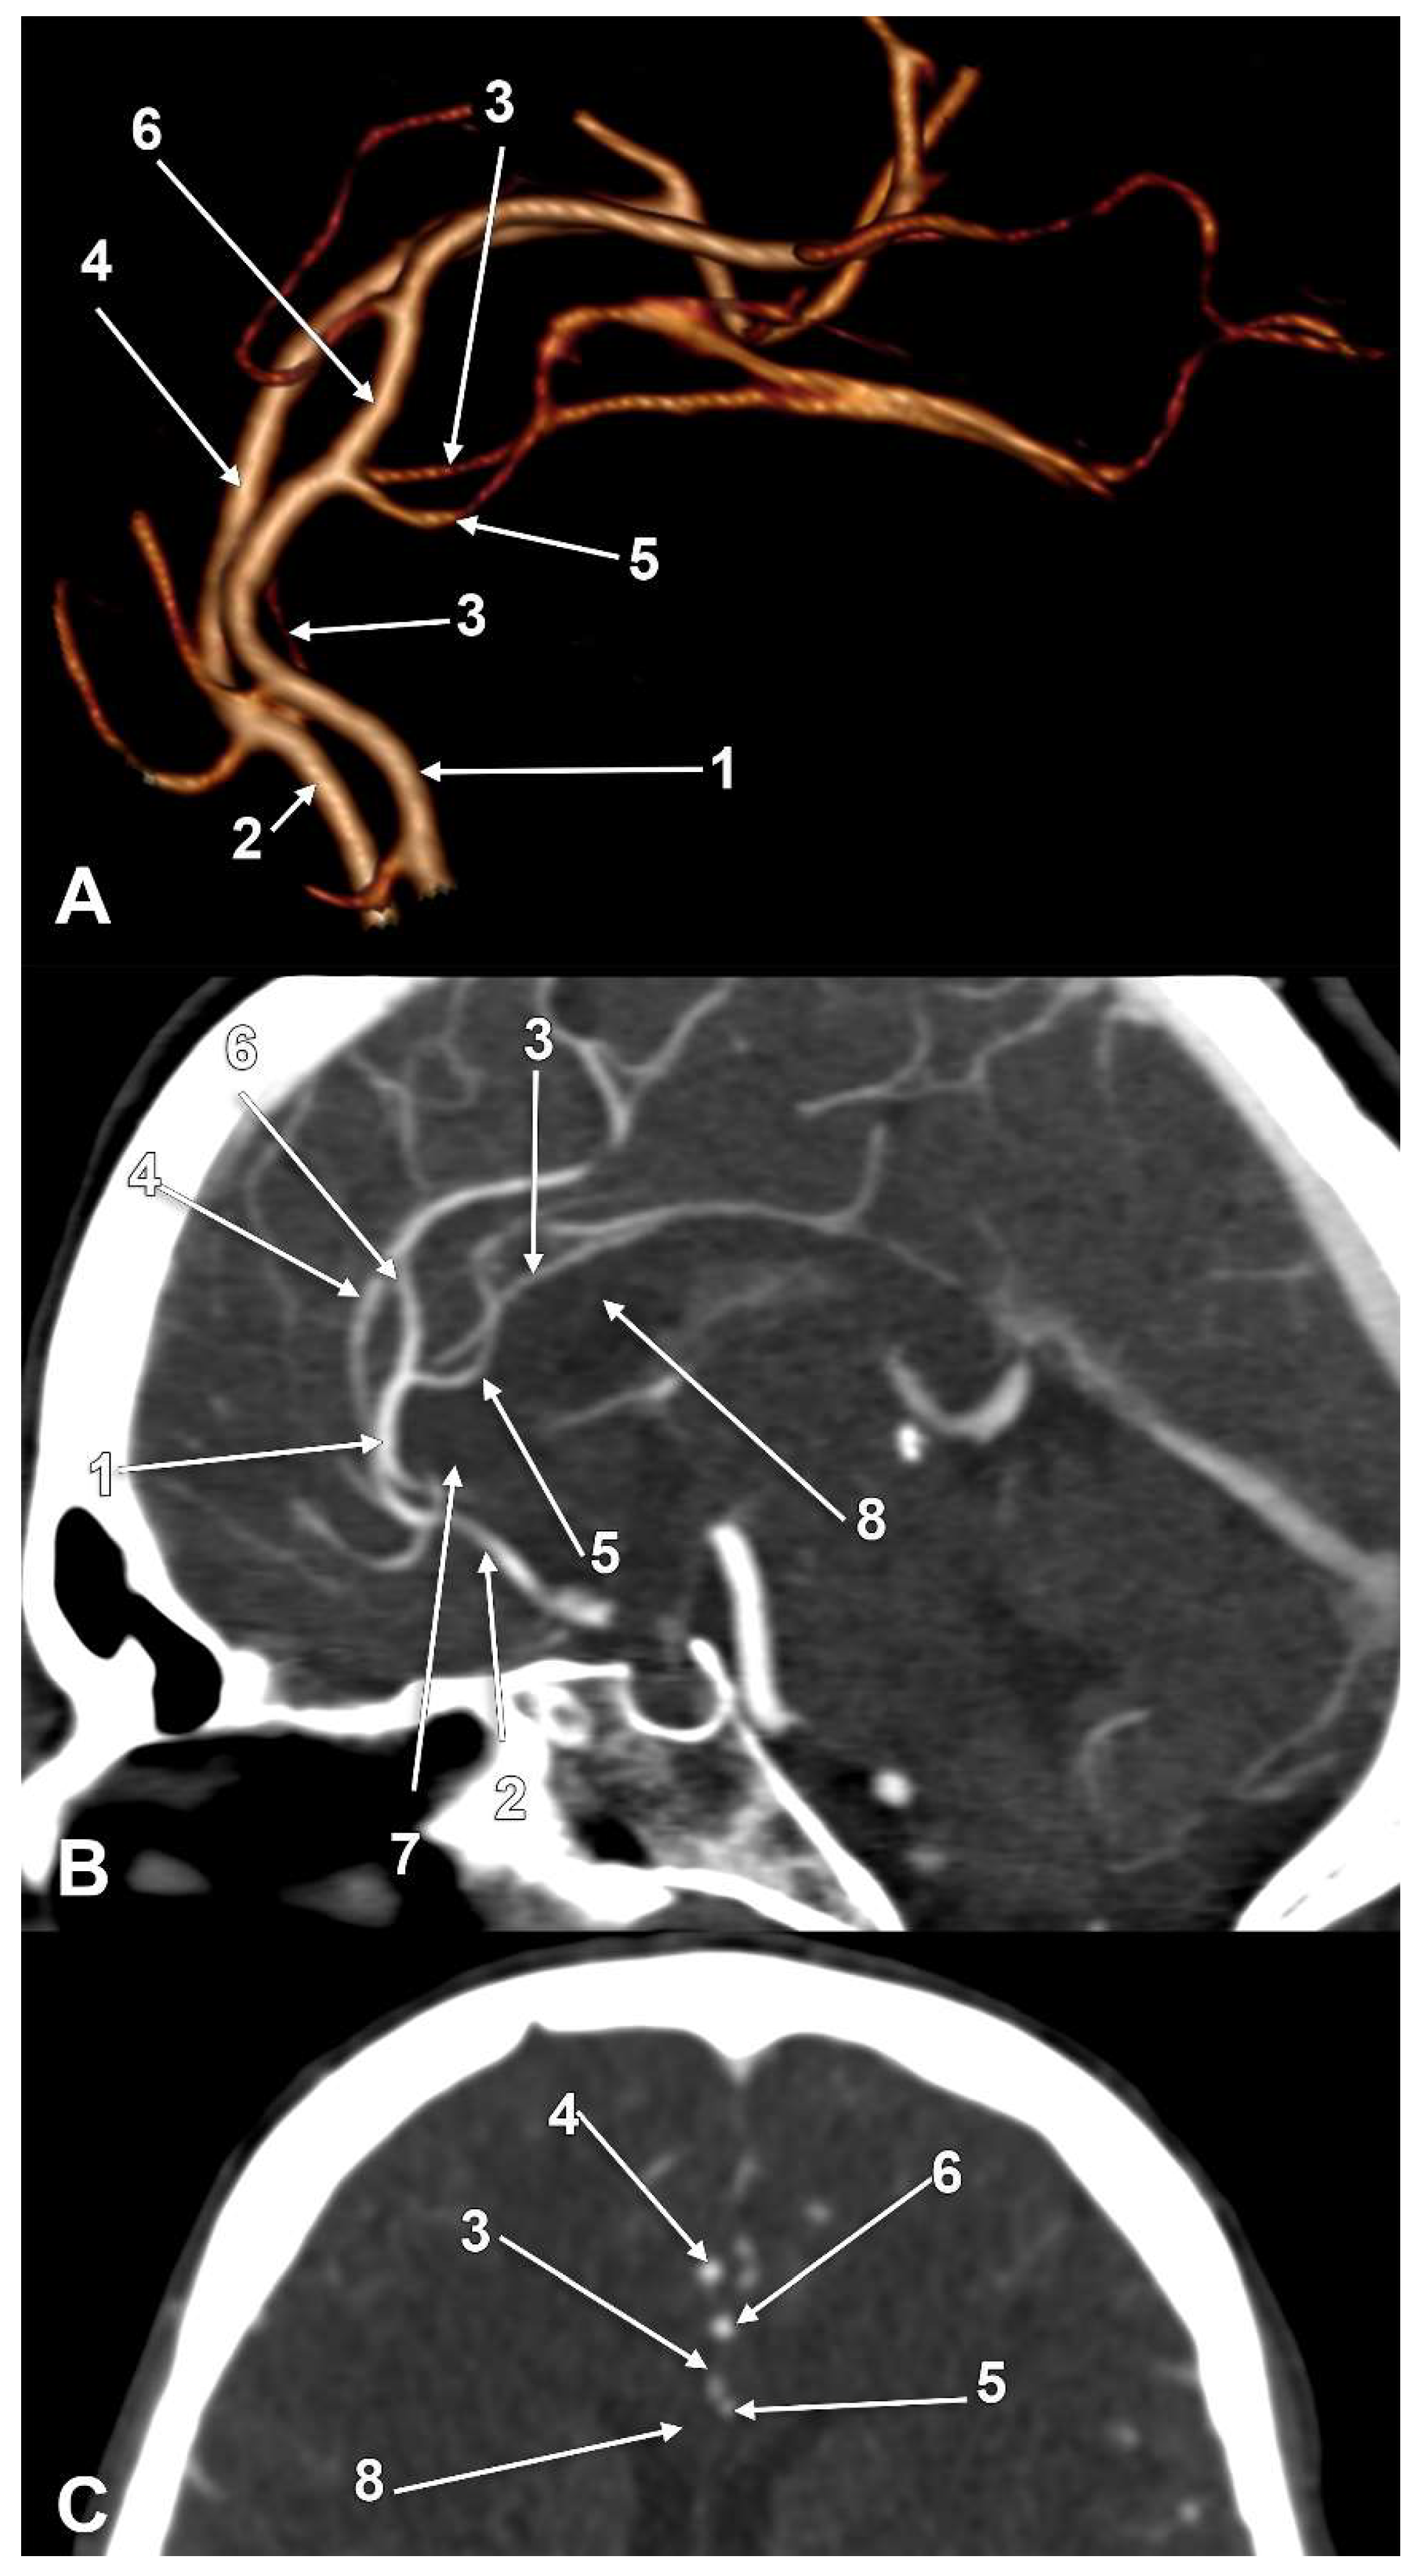

The incidences of the PCalA types, as defined in the 90 sides that were investigated, resulted in a decreasing order, as follows: PCalA type 1 (Figure 1A,C,F) was found in 46/90 sides (51.11%), type 10 (Figure 1B) was found in 13/90 sides (14.44%), type 7 (Figure 1C) was found in 7/90 sides (7.78%), type 2b (Figure 1D) was found in 6/90 sides (6.67%), type 8 (Figure 1B) was found in 5/90 sides (5.56%), types 3 (Figure 1E) and 4 (transcallosal course of the PCalA) (Figure 2 and Figure 3, Video S1) were found each in 3/90 sides (3.33%), types 2a (Figure 1E,F) and also 6 (Figure 4A), were found in 2/90 sides (2.22%), and types 5 (Figure 4B), 9 (Figure 4C), and 11 (triple PCalA) (Figure 4D) were each found in 1/90 sides (1.11%) (Table 1).

Figure 3. Type 4 pericallosal arteries coursing through the corpus callosum; (A) Three-dimensional volume rendering, left lateral view; (B) Mediosagittal slice through the corpus callosum; (C) Coronal slice through the corpus callosum: 1. left anterior cerebral artery; 2. right anterior cerebral artery; 3. right pericallosal artery; 4. right callosomarginal artery; 5. transcallosal course of the left pericallosal artery; 6. left callosomarginal artery; 7. rostrum of corpus callosum; 8. body of corpus callosum.